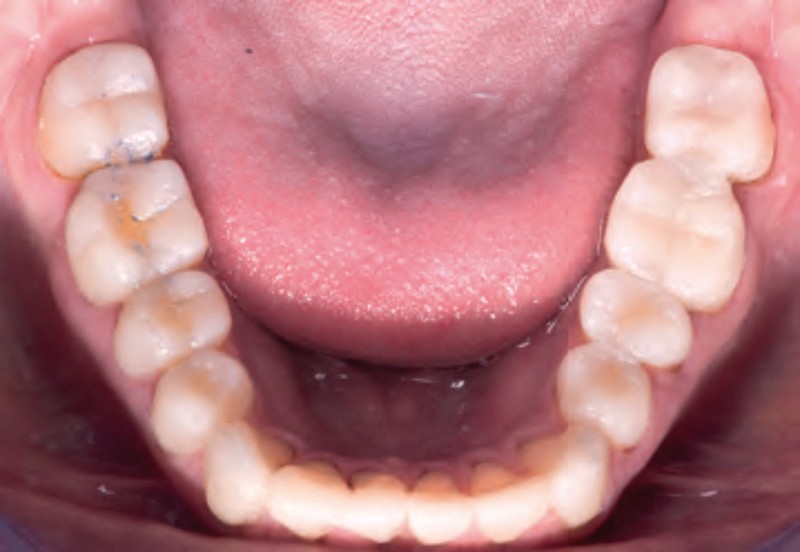

Jean-Pierre Attal : Tout à fait. Mais il faudra donner au prothésiste un maximum d’indications pour qu’il puisse réaliser sa cire de diagnostic. Vous découvrirez que la première étape de la réalisation de ces « full mock-up » est la réalisation d’un projet esthétique virtuel [8] à partir de cadrages photographiques précis aux trois échelles (visage, sourire, dento-gingivale). Gil Tirlet nous expliquera tout cela en détail avec des vidéos que j’ai déjà visionnées et qui sont très impressionnantes (fig. 1 à 4) !

Jean-Pierre Attal : Exactement, car il est possible d’appliquer le protocole de la technique « 3 steps » aux patients présentant des pertes de substance d’origine attritive (bruxisme) (fig. 5).